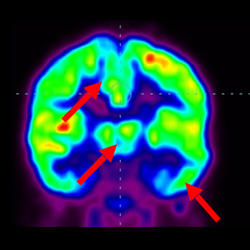

干細(xì)胞治療腦癱后改善的客觀放射學(xué)證據(jù)

細(xì)胞治療前 PET CT 掃描顯示神經(jīng)組織中的藍(lán)/黑色區(qū)域,表明腦癱引起的大腦損傷。

細(xì)胞治療后,藍(lán)色和黑色區(qū)域減少,并且看到更活躍的區(qū)域。這表明損傷減少并改善了大腦功能。

這證明細(xì)胞療法是治療腦癱兒童安全有效的方法。細(xì)胞療法可以更新大腦損傷的核心,并且可以通過 PET CT 掃描來監(jiān)測(cè)大腦的改善情況。這些細(xì)胞療法與標(biāo)準(zhǔn)治療一起促進(jìn)腦癱兒童的生長(zhǎng)和改善。